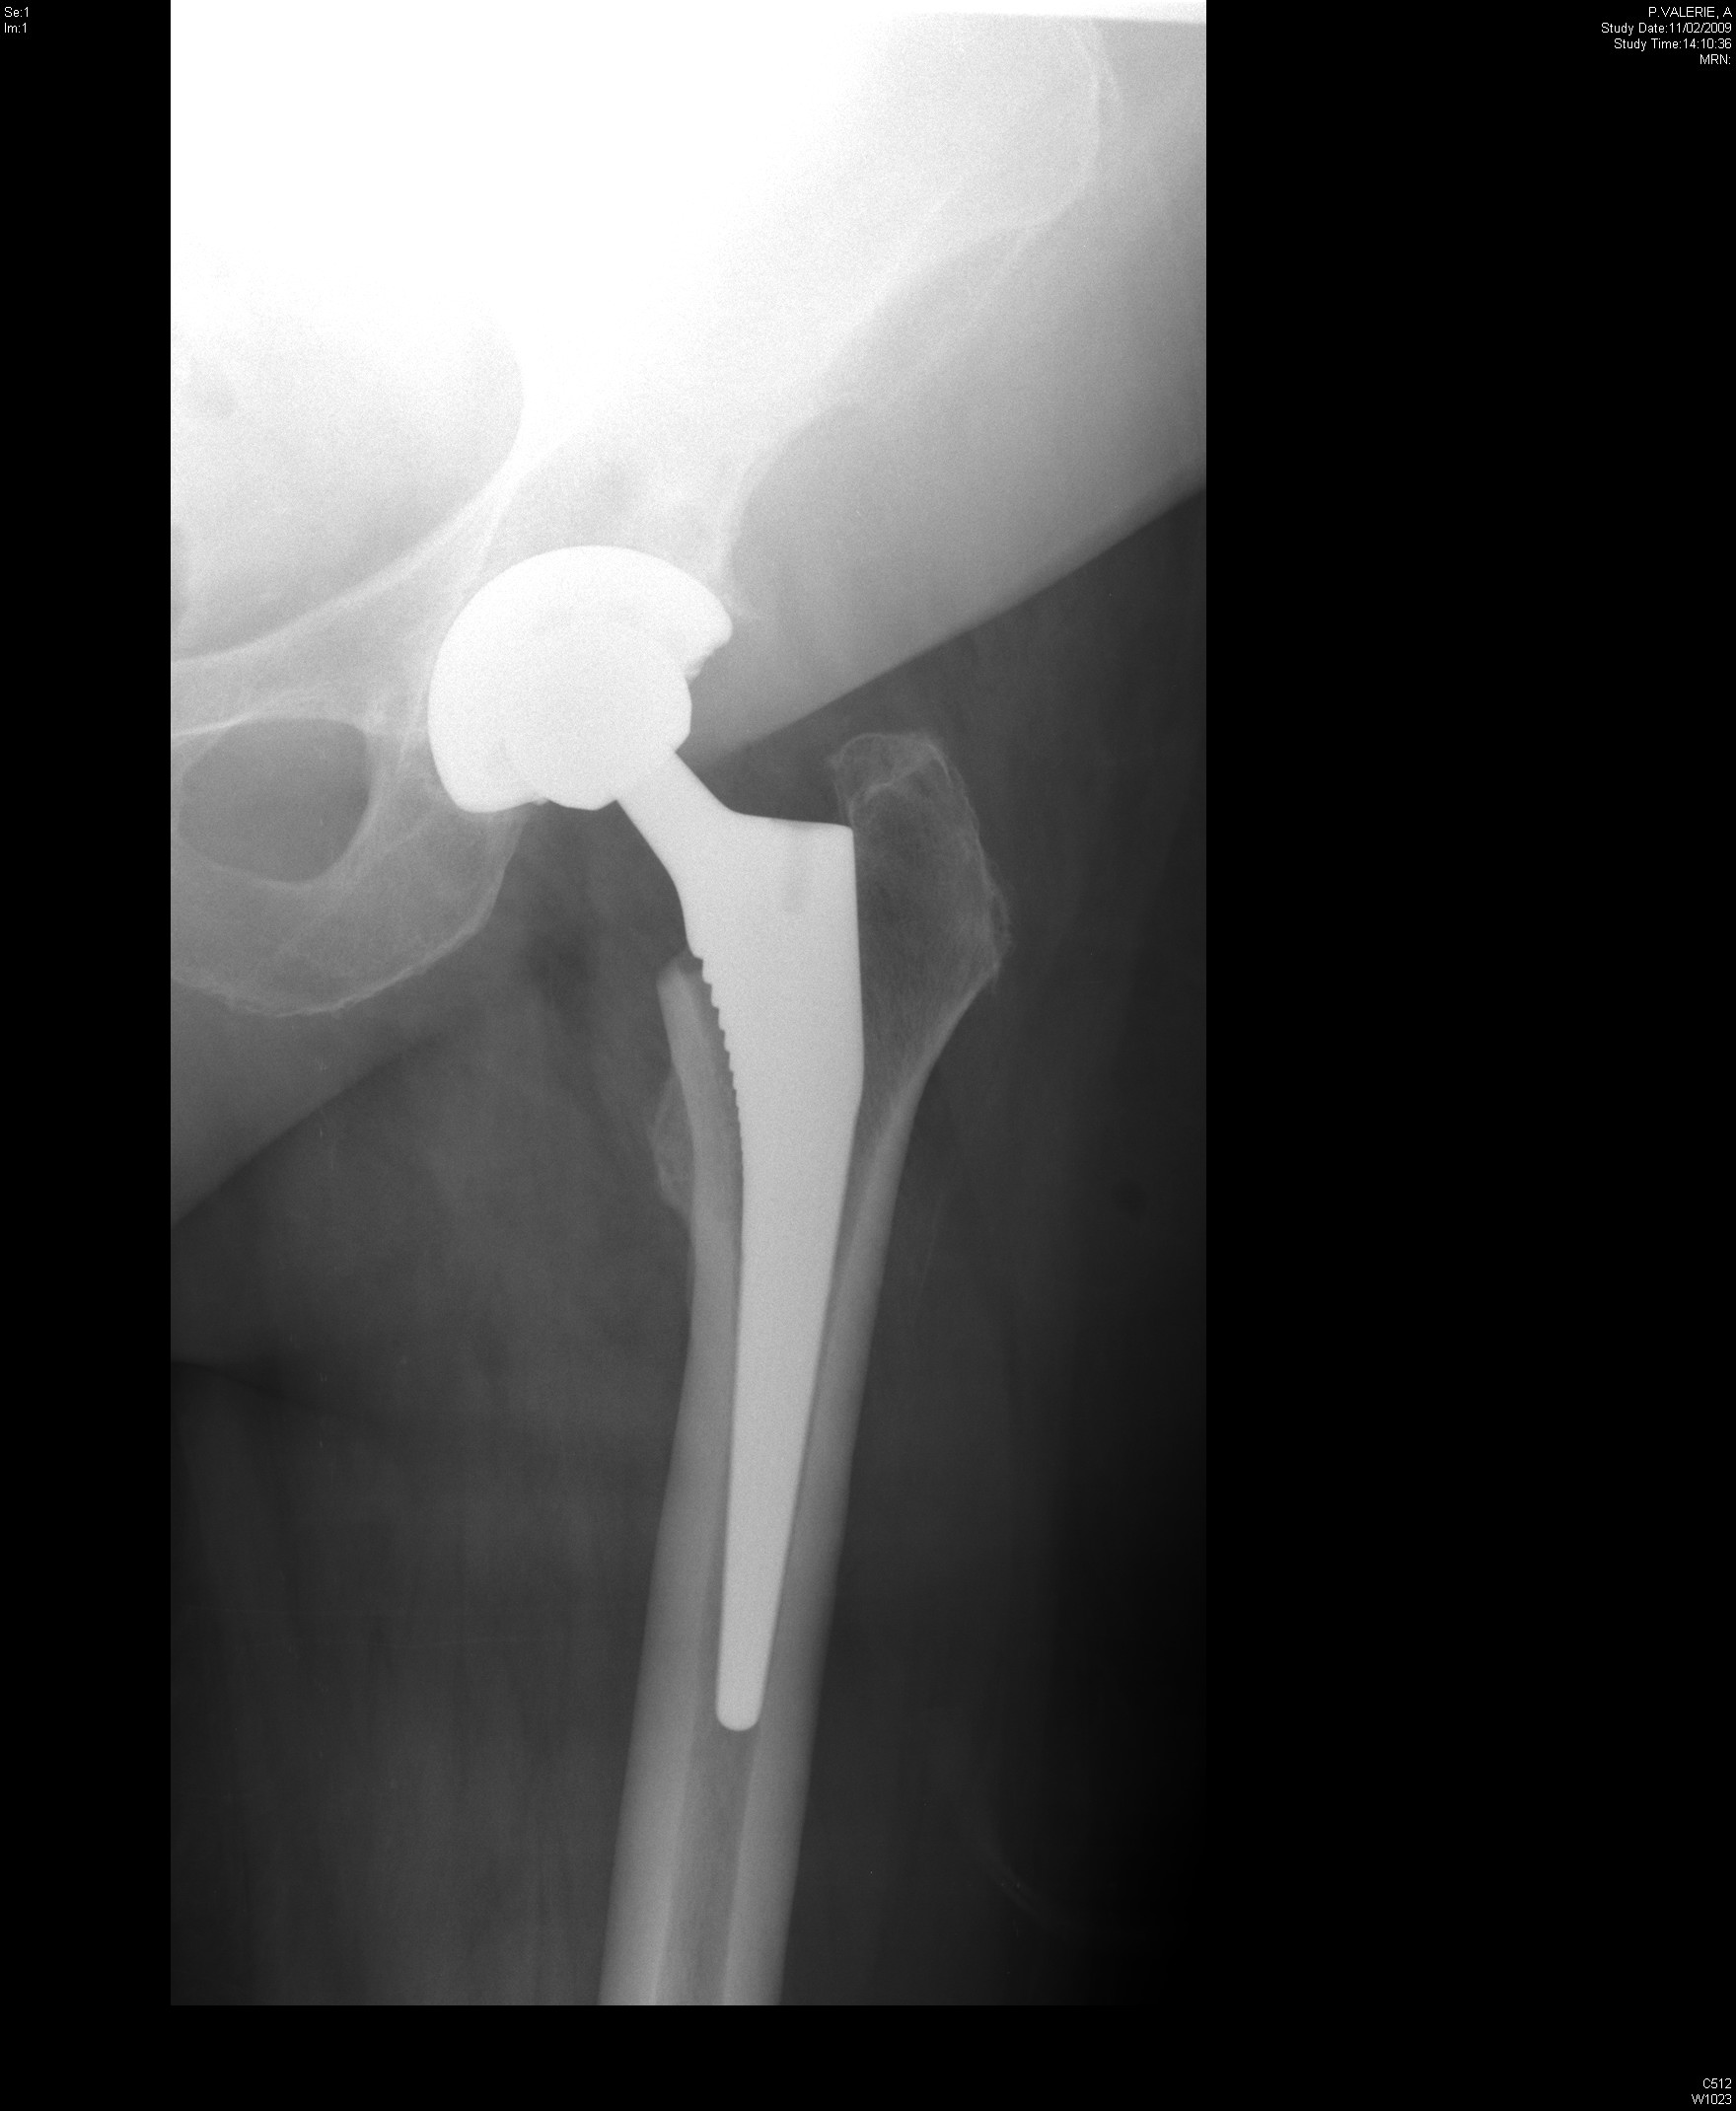

From radiopaedia.org

Dislocation of hip replacement Image Sleeping After Hip Replacement Complications “as with any surgery, there is some risk of complications during and after a hip replacement, which may include infection at the incision site, bone fractures and hip dislocations,” explains thakkar. When you’re sleeping on your back, make sure you don’t cross your ankles or legs. Hospital staff will discuss possible complications, and review with. To ensure a quick recovery,. Sleeping After Hip Replacement Complications.